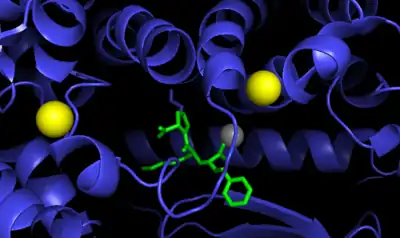

ACE is a zinc metalloproteinase.[13] The zinc center catalyses the peptide hydrolysis. Reflecting the critical role of zinc, ACE can be inhibited by metal-chelating agents.[14]

The E384 residue is mechanistically critical. As a general base, it deprotonates the zinc-bound water, producing a nucleophilic Zn-OH center. The resulting ammonium group then serves as a general acid to cleave the C-N bond.[16]

The function of the chloride ion is very complex and is highly debated. The anion activation by chloride is a characteristic feature of ACE.[17] It was experimentally determined that the activation of hydrolysis by chloride is highly dependent on the substrate. While it increases hydrolysis rates for e.g. Hip-His-Leu it inhibits hydrolysis of other substrates like Hip-Ala-Pro.[16] Under physiological conditions the enzyme reaches about 60% of its maximal activity toward angiotensin I while it reaches its full activity toward bradykinin. It is therefore assumed that the function of the anion activation in ACE provides high substrate specificity.[17] Other theories say that the chloride might simply stabilize the overall structure of the enzyme.[16]

The enzyme was reported by Leonard T. Skeggs Jr. in 1956.[30] The crystal structure of human testis ACE was solved in the year 2002 by R. Natesh, S. Schwager & E. Sturrock in the lab of K. Ravi Acharya.[15] It is located mainly in the capillaries of the lungs but can also be found in endothelial and kidney epithelial cells.[31]